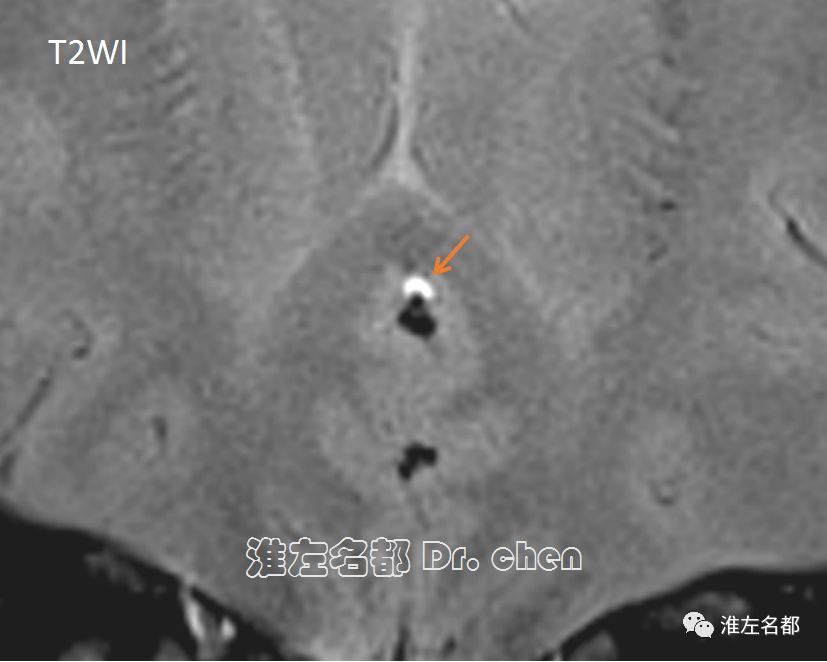

△管壁高分辨MRI之T1WI和T2WI序列:左侧大脑前动脉A2段可见“月牙形”壁内血肿高信号(亚急性期),提示动脉夹层